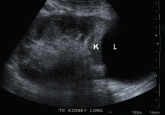

ArticleHigh creatinine 6 months after renal transplantAuthor:Anil K. Agarwal, MDPublish date: March 1, 2012Ultrasonography showed a large fluid collection compressing the transplanted kidney. What is the diagnosis?Read More